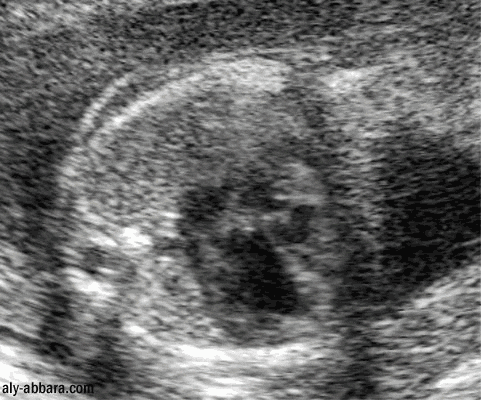

Cœur fœtal à 24 semaines d'aménorrhée

Hypotrophie du ventricule droit dans le cadre

d'un syndrome polymalformatif fœtal